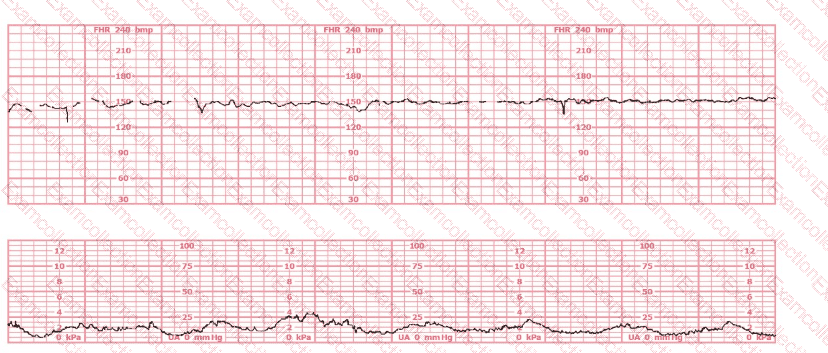

The tracing shows a clear relationship between uterine activity and fetal heart rate changes:

The uterine activity strip demonstrates very frequent contractions with little resting time between them, exceeding five contractions in 10 minutes, averaged over a 30-minute window.

As uterine activity intensifies and becomes excessively frequent, the fetal heart rate strip begins to show:

Progressive decrease in baseline

Recurrent decelerations with gradual onset and recovery

Reduced variability in the latter portion of the strip

This pattern is consistent with uteroplacental insufficiency caused by excessive uterine activity (tachysystole). NCC and AWHONN emphasize that tachysystole can result in decreased uterine blood flow and fetal oxygenation, leading to late or prolonged decelerations and eventual bradycardia if not corrected.